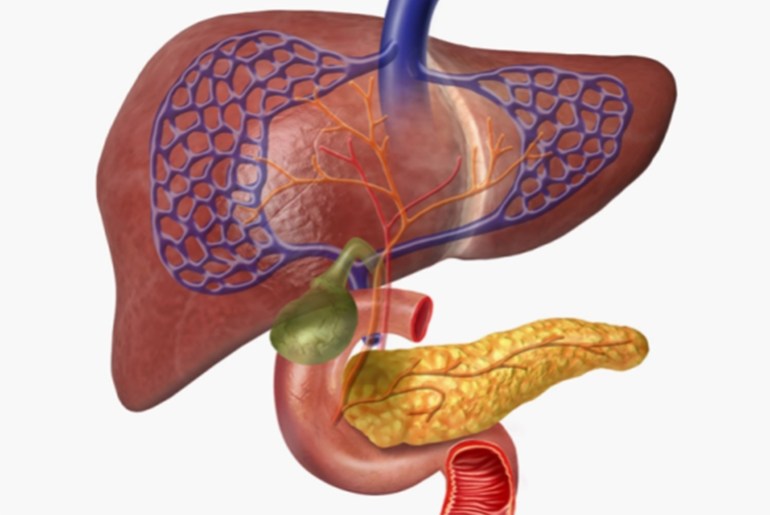

حرق وقود مختلف في “محرك” الخلية

يمكن للبشر أن يعيشوا لأسابيع بدون طعام، جزئيا لأن الجسم يحرق الدهون المخزنة، ويقوم الكبد أثناء الصيام بتحويل الدهون إلى أجسام كيتونية لاستخدامها بدلا من الجلوكوز، وهو المصدر الطبيعي للطاقة في الجسم، ووجد فريق روجيرو أن عامل بدء الترجمة في الخلايا حقيقية النواة بالكبد أصبح أكثر نشاطا، حتى مع توقف الكبد عن أنشطته الأيضية الأخرى، مما يشير إلى أن هذا العامل كان متورطا في عملية إنتاج الأجسام الكيتونية.

حدثت التغيرات نفسها في الكبد -إنتاج الأجسام الكيتونية من حرق الدهون، إلى جانب زيادة في نشاط عامل بدء الترجمة بالخلايا حقيقية النواة- أيضا عندما تم إعطاء الحيوانات المختبرية نظاما غذائيا كيتونيا يتكون في الغالب من الدهون. عندها لمعت الفكرة في ذهن الباحثين، وقال روجيرو “بمجرد أن تمكنا من رؤية كيفية عمل المسار، رأينا فرصة للتدخل”.